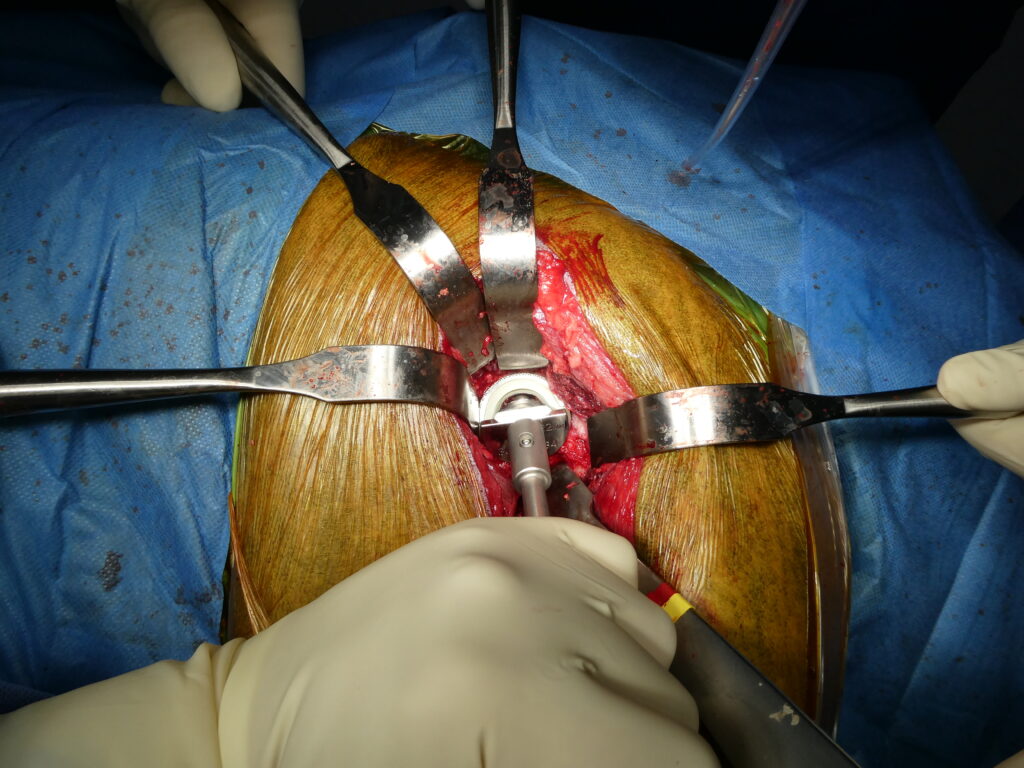

La chirurgie de prothèse totale de hanche est une intervention orthopédique majeure, réalisée sous anesthésie générale et dans des conditions strictes d’asepsie. Elle suit des étapes rigoureuses, incluant l’ablation de la tête fémorale pathologique, la préparation de l’acétabulum, la mise en place du composant acétabulaire, puis la préparation du fémur et l’implantation de la tige fémorale.

Des contrôles peropératoires permettent d’évaluer la stabilité de l’articulation reconstruite, l’amplitude des mouvements et la longueur du membre. Une fermeture anatomique soigneuse des tissus mous est essentielle pour limiter le risque de complications précoces.

Impaction de la cup après alésage de la cavité acétabulaire.